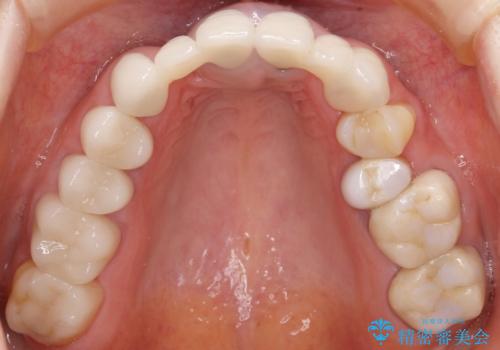

丁寧にう蝕除去と再根管治療を行い症状の改善を確認したのち、セラミッククラウン及びセラミックインレーによる補綴を行いました。

まるで天然歯のような自然な見た目と咬み心地にご満足頂けました。

気にされていた違和感もなくなり、喜んで下さいました。

クラウンの種類:オールセラミッククラウン スタンダード